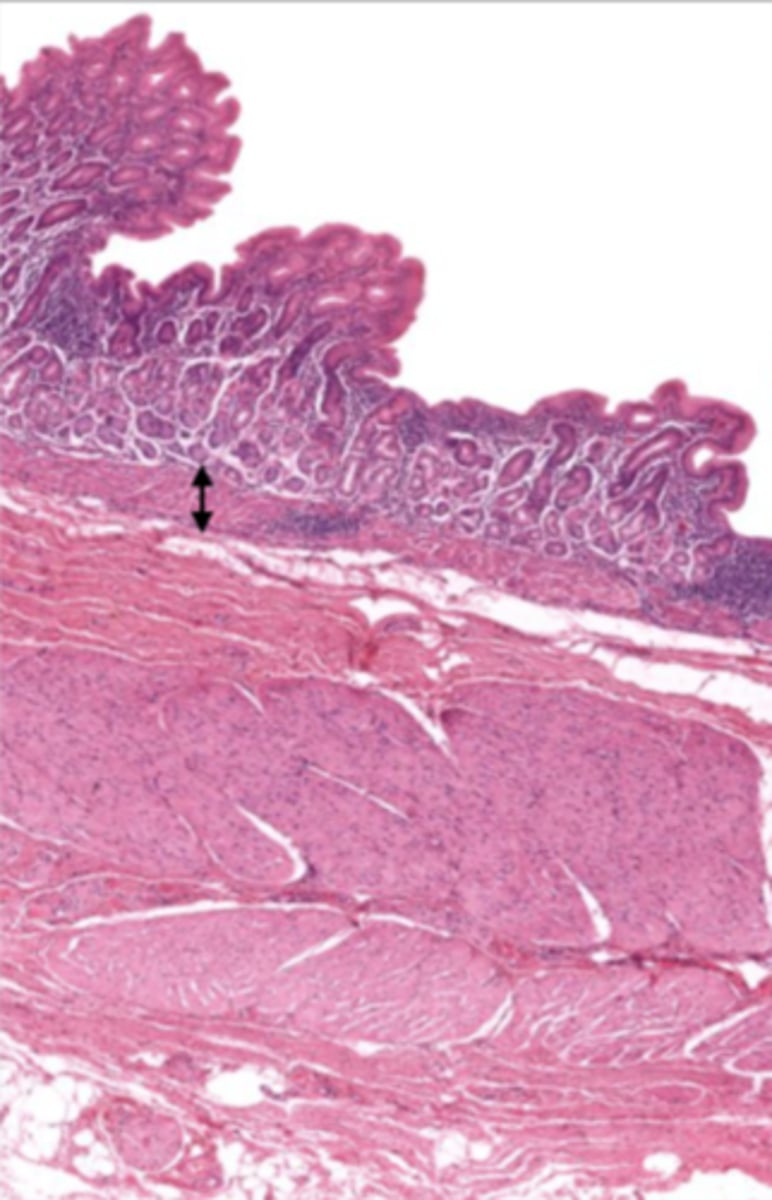

cardiac stomach (histology)

simple columnar epithelium

what kind of epithelium lines the mucosa of the cardiac stomach?

gastric pit (cardiac stomach)

lumen (cardiac stomach)

mucosa (cardiac stomach)

mucosal epithelium (cardiac stomach)

lamina propria (cardiac stomach)

muscularis mucosa (cardiac stomach)

submucosa (cardiac stomach)

contains glands and blood supply

muscularis externa (cardiac stomach)

serosa/adventitia (cardiac stomach)